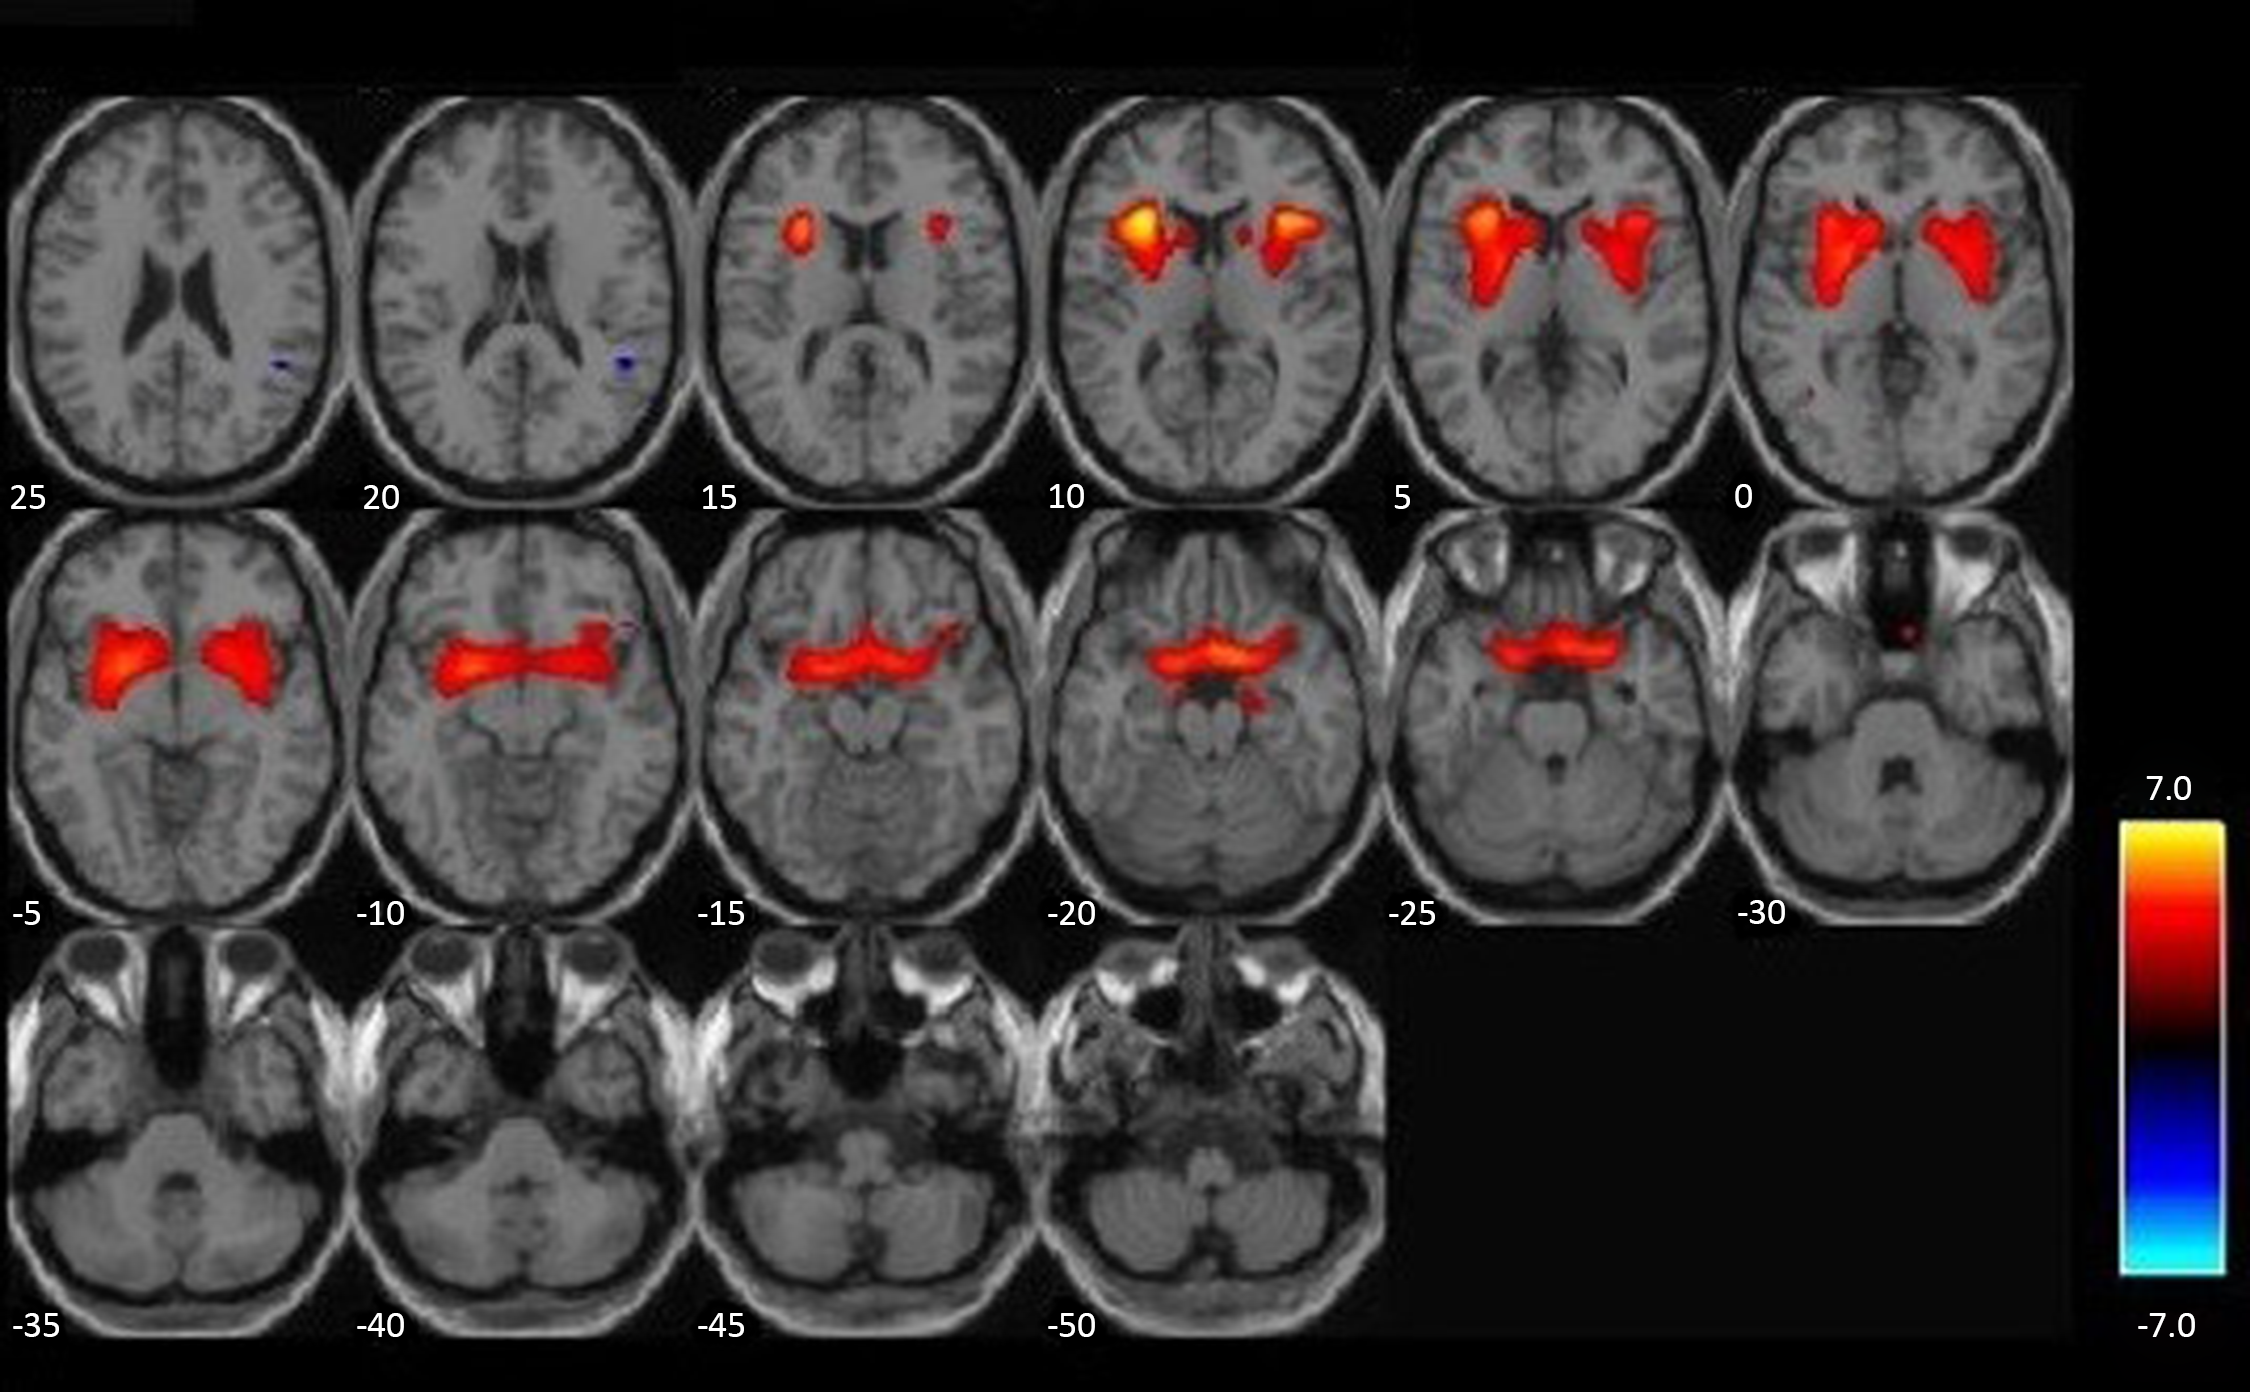

For visualization purposes, whole-brain correlations between GMV and substance use severity, controlling for age, race, IQ, PCL:YV total scores, and brain volume (gray matter + white matter), are represented in axial slices in Figure 1. These effects were thresholded to p < .005, using a cluster-based threshold of 1387 voxels (3DClusSim, Nearest Neighbor 3, allowing faces touching, edges touching, corners touching). This figure is intended to highlight the whole-brain orientation of significant effects in a priori ROIs, presented in data tables.

Figure 1. Elevated gray matter associated with substance use severity. VBM whole-brain (positive) correlations with substance use severity, p < .005, K(NN3) = 1387, and N = 152, are highlighted in orange/yellow. More severe substance use is associated with increased gray matter in highlighted regions. Covariates of age, race, IQ, PCL:YV, and total brain volume (GM + WM) are included in this analysis.